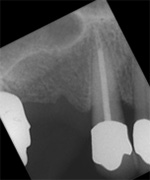

Die ersten beiden Aufnahmen sind aus dem Jahr 1999, die 3. von 2006

Der umfangreiche kariöse Defekt steuerte sehr bald hin auf die komplette Entfernung des Zahninnen­gewebes mit anschliessendem medikamentösen Wiederverschluss. Aufbissempfindlichkeit am Folgetermin ist immer Aufforderung zur erneuten Intensivsuche nach weiteren Kanälen, die hier einen 4. Ast zum Vorschein brachte. Nach 2 ausgelassenen Terminen

waren vorrangig Wiederherstellung von desinfizierender Einlage und provisorischer Füllung angezeigt. Eine weitere Woche später wurde in allen Kanälen das Medikament durch die endgültige Verschlussmasse ersetzt, worauf Zahn 36 mit 12-tägiger Verzögerung erneut zu rebellieren begann. Das hiess aus den hinteren Wurzeln Füllmaterial wieder raus und

Einlage erneut rein. Als es dann 4 Wochen später bei der hinteren Wur­zel aussen anzuschwellen begann und ein Medikamentenwechsel ohne Wir­kung blieb, wurden die hinteren Ka­näle abgefüllt und auch in gleicher Sitzung das überstopfte Material (Bild 1) mittels Resektion (Bild 2) von aussen entfernt.